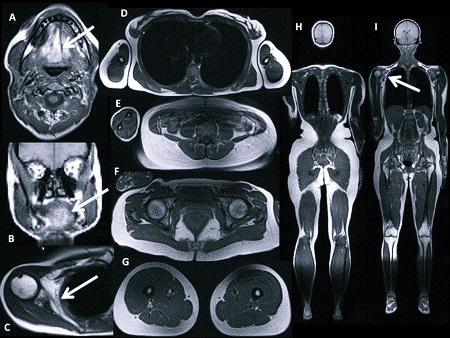

При помощи МРТ можно увидеть практически все органы и системы человека. Нередко именно томография помогает точно поставить диагноз. Если на проведение данной процедуры есть показания, не стоит ее бояться, тем более, она может спасти жизнь.

Пациента кладут на специальный стол, расположенный возле мощного сканера. Постепенно сканер движется вдоль стола или наоборот. На компьютер со специальной программой отправляются данные о состоянии определенного органа или целой системы. Врач может визуально их увидеть, причём даже в трехмерном виде. В среднем диагностика занимает около получаса, в зависимости от обследуемого органа (брюшная полость сканируется дольше всего и может затянуться на час).

В результате врач получит подробные снимки органов и систем в нескольких плоскостях. Такой метод поможет поставить точный диагноз и выявить патологию на ранней стадии. Сканирование предоставляет самую полную информацию об обследуемом органе.

Пациента укладывают на особую площадку, которая непрерывно движется. На мозг при этом воздействует сильное электромагнитное поле. На аппаратуру подаются данные – реакция ядер водорода после мощного электромагнитного импульса. Как показали детальные исследования, никакого вреда ни мозгу, ни другим органам при этом не наносится. Польза от таких исследований в сотни раз выше, чем возможные риски. Никаких побочных явлений ждать не стоит. А вот эффект просто колоссальный. Можно в деталях и разных проекциях увидеть тело человека изнутри.